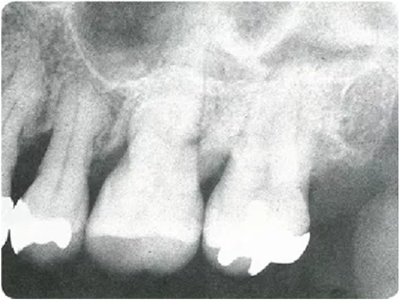

● X片的種類

牙周探診在掌握眼睛看不到的部分的狀態(tài)方面,是非常重要的一個(gè)檢查。參考X片進(jìn)行探診,可以立體掌握該檢查部位。

因此,在檢測(cè)牙周袋深度時(shí),通過 X 片確定牙槽骨的狀態(tài)、根的形態(tài)、牙結(jié)石的附著狀態(tài)等,在腦中有一個(gè)大致的印象,應(yīng)該可以很大程度上減少漏檢。

僅通過口腔視診是無法看出何處有骨吸收的。通過拍攝的牙片,可以一定程度上掌握牙槽骨吸收的情況。

如果觀察X片后預(yù)想的狀態(tài)和牙周探診分析出的狀況有很大差異,就需要再次注意此部位并重新做一次牙周探診。